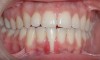

Fig 14. Post-orthodontic Miller Class II recession treated with a combined orthodontic-surgical approach. Clinical view 5 years after first orthodontic treatment showing GR of right lower incisor and a labially prominent root.

Figure 14

Fig 15 Same patient 2 years later showing worsening of GR and inflammation.

Figure 15